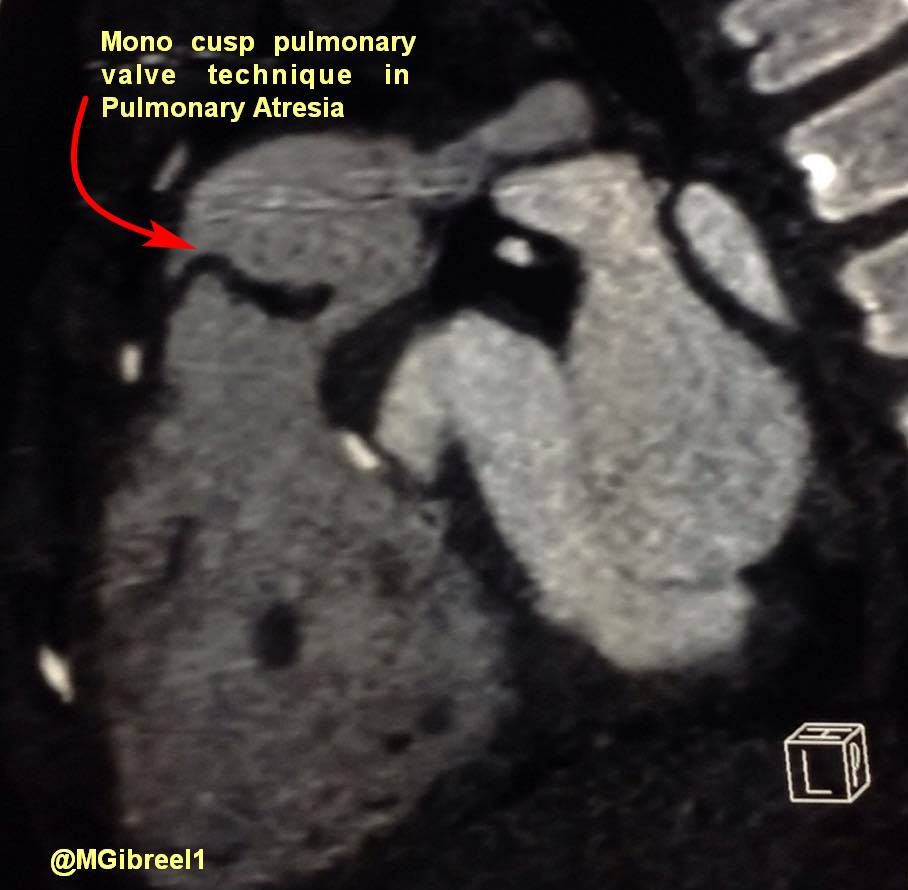

Mono cusp Pulmonary valve technique in Pulmonary Atresia

Mohamed Gibreel , FEBR (Fellowship of Egyptian Board of Radiology ) Cardiac imaging consultant at Aswan heart center -Magdi Yacoub Foundation , Egypt